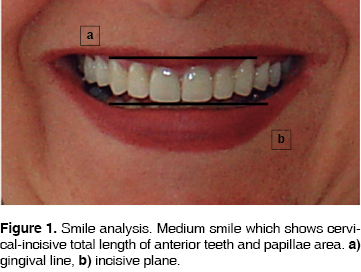

The line of the smile must be assessed in a diversity of situations: at rest, during speaking and when smiling. During a full smile, the upper lip must rest at the level of medium-facial gingival margins of the upper front teeth. The lower lip must rest at the incisive borders of upper anterior teeth (Figure 1). In a full smile instance, the incisive borders of these teeth must run parallel to the curvature of the lower lip.